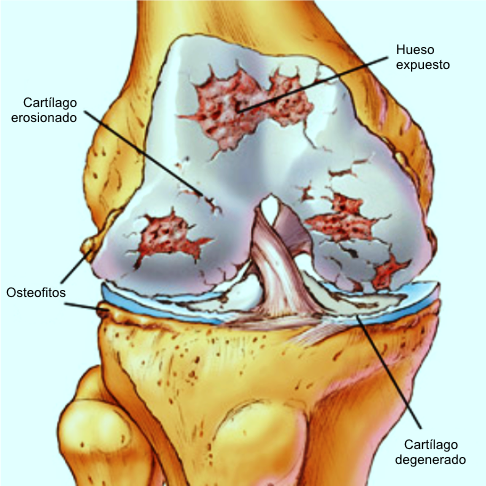

Cambios asociados con artrosis

La artrosis es una enfermedad articular degenerativa no inflamatoria caracterizada por degeneración del cartílago articular, hipertrofia ósea en los márgenes y cambios en la membrana sinovial. A diferencia de la artritis, donde el daño comienza en la sinovial, en la artrosis inicia en el cartílago.

La artrosis presenta áreas focales de daño al cartílago con fibrilación y pérdida de volumen. Las lesiones se inician en las zonas de mayor contacto, progresan en profundidad hasta exponer el hueso subcondral. Se pierde la matriz (proteoglicanos) y más tarde la red de colágeno. Los condrocitos forman clones, son metabólicamente activos, pero sintetizan proteoglicanos de composición anormal sensibles a proteasas.

En fases avanzadas se destruye la red de colágeno, se expone el hueso y mueren los condrocitos. El turnover normal de la matriz es bajo, pero en la artrosis hay desequilibrio entre síntesis y degradación, y los condrocitos ya no pueden mantener la homeostasis.

En fases terminales, la superficie del cartílago se vuelve rugosa y perforada, alterando la movilidad articular y afectando también hueso, cápsula, sinovial y tendones.

El hueso subcondral reacciona con esclerosis y formación de osteofitos. Puede formarse neocartílago desde el hueso. La sinovial reacciona a los fragmentos del cartílago con sinovitis y posibles cristales cálcicos.

🔬 Anatomía patológica

El dato más significativo de degeneración artrósica del cartílago articular lo constituye la pérdida de su característico brillo azulado y lisura, para tornarse de un color amarillento y felpudo, con menor consistencia y firmeza.

• Fase IV: Ulceración. Aparición del hueso subcondral en la superficie articular, debido a la desaparición total del cartílago.

Cartílago articular. La anormalidad más temprana es un aumento en el contenido de agua del cartílago. Luego se produce la desintegración de las grandes moléculas de condromucoproteínas y pérdida de proteoglicanos. Estos cambios se atribuyen a la insuficiencia por fatiga de la red del colágeno. A medida que el cartílago se vuelve edematoso y blando, la lesión secundaria de los condrocitos puede causar desintegración progresiva de la matriz por liberación de enzimas celulares. La deformación del cartílago añade sobrecarga a la red del colágeno. Los primeros signos visibles son el reblandecimiento y disociación de la superficie del cartílago. Las hendiduras se hacen más acentuadas, hasta llegar al desgaste evidente o fibrilación. Las alteraciones tempranas (condromalacia) no son reversibles, pero no siempre progresan hasta la destrucción completa. Hay indicios de intentos de reparación con acumulación de condrocitos y aumento de síntesis de proteoglicanos en algunos casos.

Hueso. Se observa aumento de vascularidad y actividad del hueso subcondral, con áreas de esclerosis y quistes subcondrales en zonas de sobrecarga. El hueso reacciona con engrosamiento, visible en radiografía como esclerosis. Las fisuras en la placa subcondral transmiten presión al hueso esponjoso, favoreciendo formación de quistes. La pérdida progresiva de cartílago puede conducir a abrasión y exposición ósea.

Borde o margen articular. Con la inestabilidad, el cartílago intacto prolifera y se osifica, generando osteofitos y condrofitos. Esta remodelación intenta restaurar la congruencia articular, aunque se asocia a malposición progresiva. El resultado final depende del equilibrio entre destrucción (pérdida de cartílago, fragmentación ósea) y reparación (osteofitosis, esclerosis).